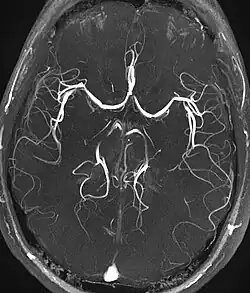

Angiografia

A angiografia por ressonância magnética (MRA) gera imagens das artérias para avaliá-las para estenose (estreitamento anormal) ou aneurismas (dilatação da parede vascular, em risco de ruptura). O MRA é frequentemente usado para avaliar as artérias do pescoço e do cérebro, a aorta torácica e abdominal, as artérias renais e as pernas (chamado de "escorrer"). Uma variedade de técnicas podem ser usadas para gerar as imagens, como a administração de um agente de contraste paramagnético (gadolínio) ou usando uma técnica conhecida como "aprimoramento relacionado ao fluxo" (por exemplo, sequências de tempo de voo 2D e 3D), onde a maior parte do sinal em uma imagem é devido ao sangue que recentemente se mudou para esse plano. As técnicas que envolvem acumulação de fase (conhecida como angiografia por contraste de fase) também podem ser usadas para gerar mapas de velocidade de fluxo com facilidade e precisão. A venografia por ressonância magnética (MRV) é um procedimento similar que é usado para imagens de veias. Neste método, o tecido agora está excitado inferiormente, enquanto o sinal é recolhido no plano imediatamente superior ao plano de excitação - criando assim o sangue venoso que recentemente se moveu do plano excitado.[52]